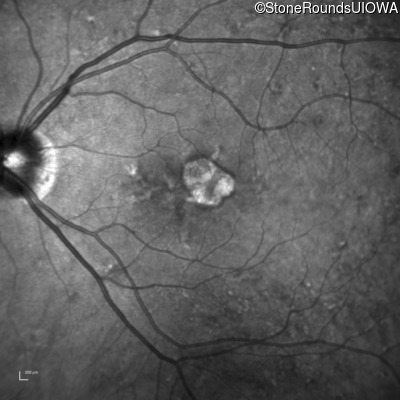

Infrared Fundus Photograph - Left - 20/40 +1

Exemplar